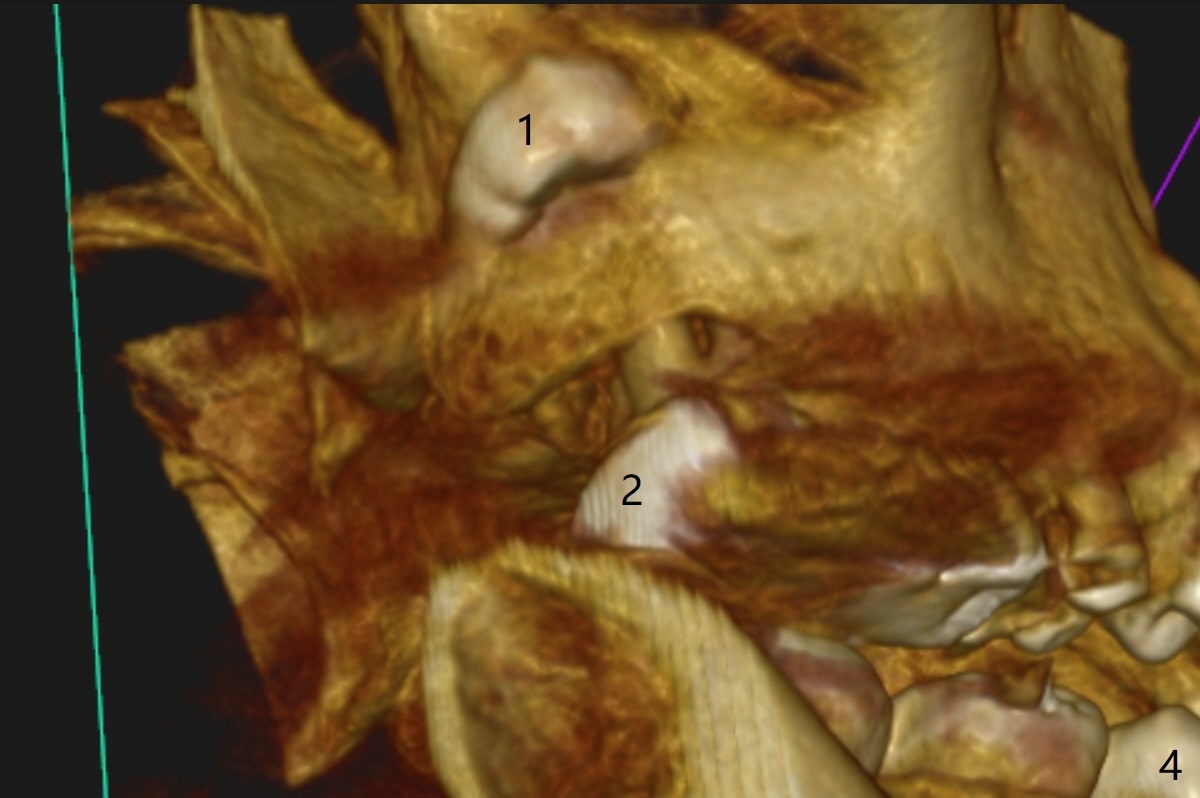

The tooth #1 should have been extracted buccodistally (Fig.3,4). Three or 4 months later, a 5x10 mm implant could be placed distopalatally superiorly to avoid removing the tooth #1 with ~ 1.5 mm clearance (Fig.5). To place an implant in orthopedic manner, the tooth #1 will be removed, while the implant should be longer (5x13 mm) to engage the bone superior to the socket of the tooth #1 (Fig.6).